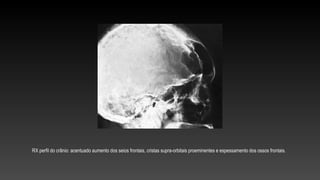

RX perfil do crânio: acentuado aumento dos seios frontais, cristas supra-orbitais proeminentes e espessamento dos ossos frontais.